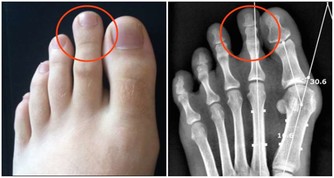

屈光不正

在靜止狀態下,平行光線經眼屈光系統的折射後聚焦於視網膜上,這便是正視眼。若平行光線經眼屈光系統的折射後不能聚焦於視網膜上,這是非正視眼,稱為“屈光不正”。屈光不正包括近視、遠視及散光。特別是患高度近視而沒有得到及時矯正,最易導致“視網膜脫離”(就是視網膜感光層與其下層組織之間的分離),是引發失明的重要原因。